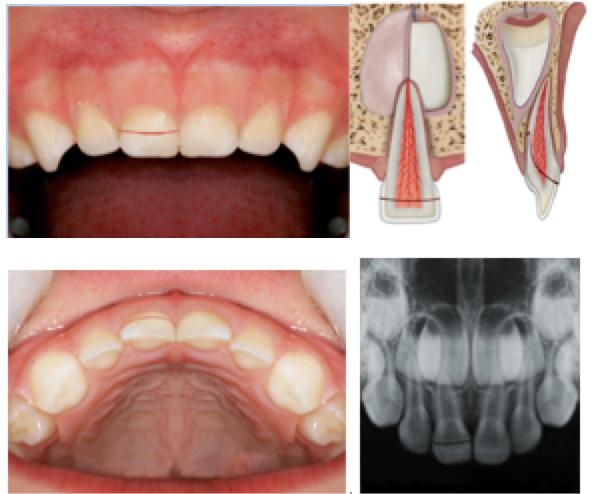

冠根折未涉及牙髓(乳牙)

A 基本描述:

折裂线涉及牙釉质,牙本质和牙骨质的牙体缺损,牙髓未暴露。

折裂线的定位:折裂涉及牙齿的冠部和牙根,并且处于水平或斜切面中。X射线检查通常仅揭示折裂的牙冠部分而不是根尖部分。

描述

折裂线涉及牙釉质,牙本质和牙骨质的牙体缺损,但未暴露牙髓

视诊

冠折裂延伸到龈缘下方。冠折裂成两个或更多个片段,其中一个是移动的

放射学检查 根尖向的折裂折通常不可见

放射推荐 咬合片